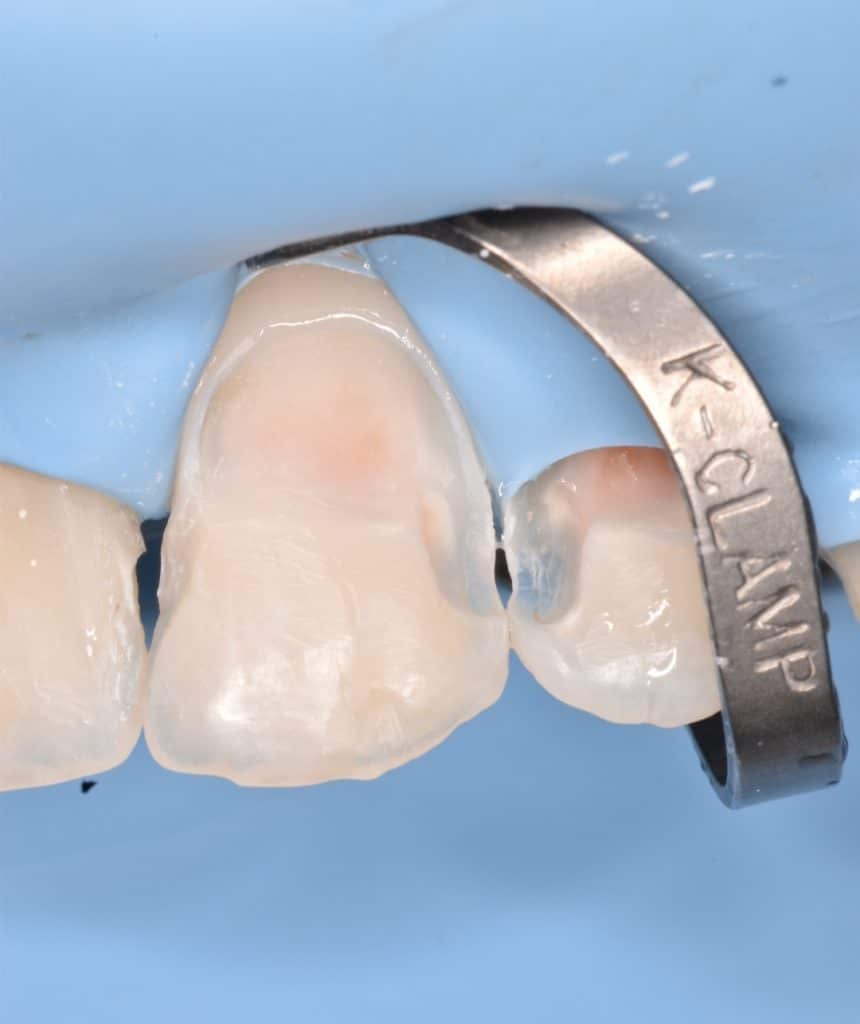

After completing the central now Lateral incisor isolation

Cavity prep.

IDS ,RC ,DWT and APX composite for dentin replacement and tokuyama composite for enamel replacement